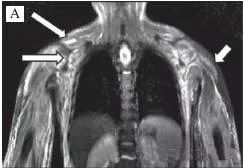

四、肌肉MRI:

四肢近端肌肉等出现炎性渗出表现。

五、肌肉活检行病理检查:

取近端肌肉如三角肌、肱二头肌,股四头肌等部位,有时候可结合肌肉MRI影像显示肌肉炎性渗出明显的地方取材,提高阳性率。